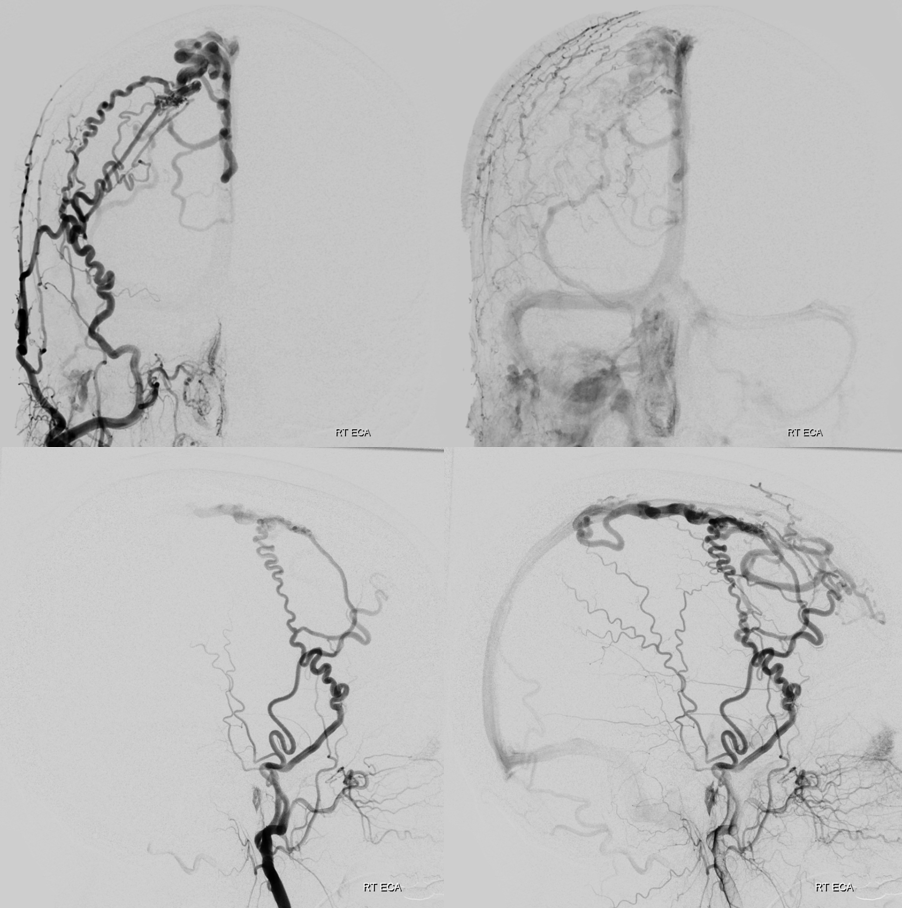

Access is challenging but not impossible with the right tools

Micro angio and onyx 18 cast. A mistake is made here

Reflux

Still alive. Why? Onyx is not adhesive etc etc? No…

How’s them apples. Reaccess is possible….

This shows the mistake. Can u see?

nBCA — its not that Onyx or nBCA is better. From this position Onyx will not reach for sure so nBCA is the way to go

Glue reflux

Closed

Now, look at the images below and tell me what the mistake during first injection was. The images on right should read post embo 1